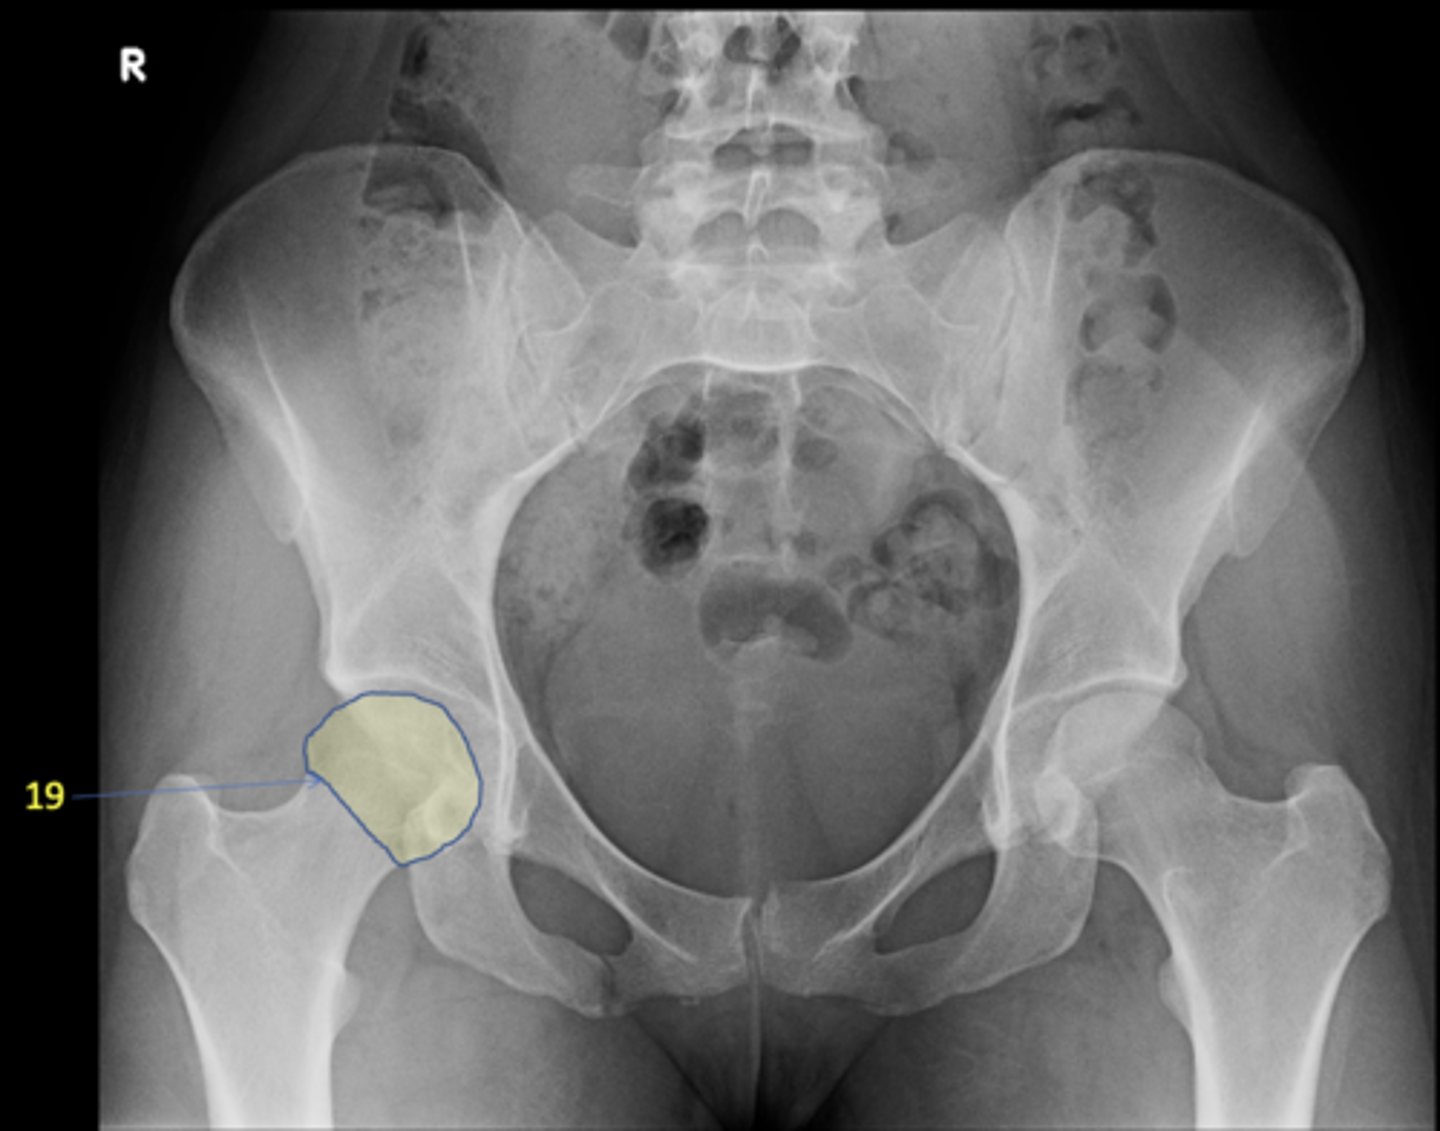

1

AP pelvis

17

Right femoral head

ID 19